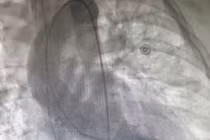

Bệnh nhi N.N.A.N. bị rối loạn nhịp tim nhập viện tại Bệnh viện Trung ương Huế.

Ngay trong đêm, các bác sĩ đã khẩn trương hội chẩn đa chuyên khoa và êkíp ECMO nhi, Gây mê Hồi sức tim, Ngoại Lồng ngực Tim mạch đã tiến hành đặt VA - ECMO để hỗ trợ tim ngay lập tức cho bệnh nhân N.N.A.N. Sau 5 ngày chạy ECMO, chức năng tim bệnh nhi N.N.A.N. dần hồi phục nhưng nhịp tim vẫn còn rối loạn rất nặng (block nhĩ – thất cấp 3) nên sau đó bệnh nhi N.N.A.N. được phối hợp thêm với khoa Can thiệp Tim mạch để tiến hành vận chuyển bệnh nhi đến phòng mổ, đặt máy tạo nhịp và cai ECMO.

Hơn 2 tuần điều trị tại Bệnh viện Trung ương Huế, bệnh nhi N.N.A.N. dần cải thiện ngoạn mục, nay có thể đi lại bình thường, chức năng tim cải thiện tốt, các chỉ số huyết động và cận lâm sàng về lại bình thường và dự kiến sẽ được ra viện vào ngày 20/3. Đây là bệnh nhi thứ 6 được thực hiện thành công kỹ thuật VA – ECMO và có cân nặng nhỏ nhất (17kg).